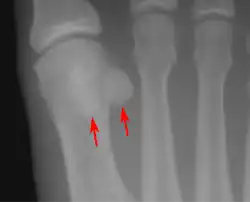

Sesamoid bones at the distal end of the first metatarsal bone of the foot.

• One or both of the sesamoid bones under the first metatarsophalangeal joint (of the great toe) can be multipartite – in two or three parts (mostly bipartite – in two parts).[12]